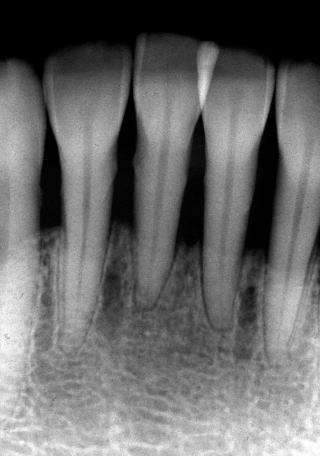

(図1)初診時(1975年10月15日)、38歳。歯肉出血が主訴で紹介された。当時、歯周疾患治治療は一部の臨床家以外はあまり関心が払われていなかった

(図3)初診から2年後(1977年7月)、40歳。Splintせずに機能している

★歯周病の治療とは、20年30年と抜かずに、口腔内が健康でQOLを維持できることである★

★生活習慣病のため短期間で治癒する病気ではない★